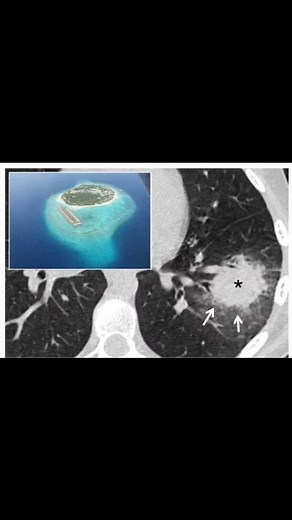

Halo sign and air crescent sign radiological findings seen in lung infection, invasive aspergillosis

The halo sign and air crescent sign are radiological findings often seen in the context of certain lung infections, particularly invasive aspergillosis. Here's a brief overview of each: Halo Sign Appearance: A ground-glass opacity surrounding a pulmonary nodule or mass. Cause: Typically caused by hemorrhage around the nodule. Associated ...